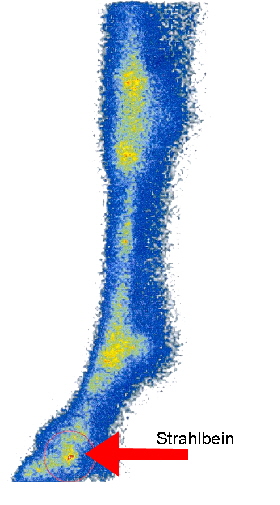

Durch eine so genannte Gamma-Kamera wird die Strahlung aufgefangen und auf dem Computerbildschirm ein farbig kodiertes Bild erzeugt. Aktive Regionen werden mit rot über gelb bis weiß dargestellt, nicht aktive Bereiche stellen sich blau dar.

Der Einsatz der Szintigrafie bei der Strahlbeindiagnostik ist begrenzt, da die Auflösung der Bilder sehr grob ist. Die Szintigrafie wird hier aber zum Beispiel eingesetzt, wenn durch Anästhesien die Lahmheit auf den unteren Bereich der Zehe eingegrenzt worden ist, aber auf Röntgenaufnahmen gleichzeitig an verschiedenen Strukturen Befunde auftreten und unklar ist welche Befunde für die Lahmheit verantwortlich sind. Die Szintigrafie stellt dann die aktiven Regionen als “hot spots” dar, womit die Ursache der Lahmheit geklärt werden kann.

Auch wenn trotz positiver Anästhesie kein entsprechender Röntgenbefund gefunden wird, ist eine Szintigrafie sinnvoll, da sie im Krankheitsverlauf früher als die Röntgenuntersuchung Veränderungen zeigt. Oder, wenn die Lahmheit zu gering ist, um zu anästhesieren, kann die Szintigrafie als “screening” bzw. Suchverfahren eingesetzt werden, um einen “hot spot” zu finden.